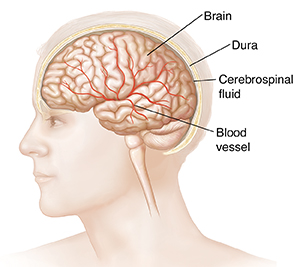

Inside the skull

Under the scalp and the skull, a tough membrane (called the dura) surrounds the brain. Beneath the dura, cerebrospinal fluid (CSF) cushions the brain. Blood vessels carry nutrients and oxygen-rich blood throughout the brain.

| Blood vessels carry blood throughout the brain. |